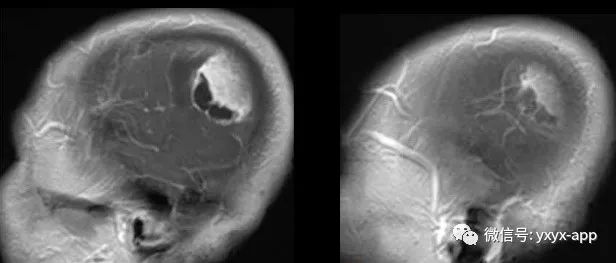

中年男性,间断头痛3月余,请诊断!

医学影像  yxyx-app  医学影像APP,打造伴随医生快速成长的影像学习社区。与影像园(Xctmr.com)一起提供最全面的影像案例库、基础(解剖、病理、影像诊断)知识、影像技术及考题等,为医生提供最佳的医学影像参考。【所属科室】神经外科【基本资料】患者,男,56岁【主诉】间断头痛3月余【现病史】患者于3月前无明显诱因下出现头痛,性质为胀痛,改变体位后可诱发或加重症状,呈间断性,持续数分钟后自行缓解,近1月出现头痛较前加重,持续时间较前延长。...